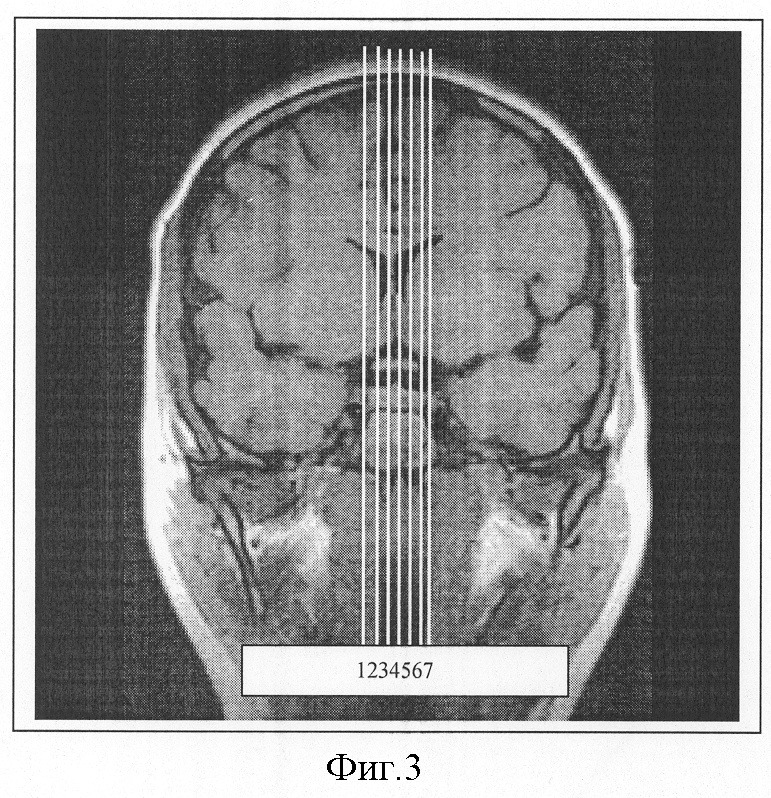

На фиг.3 показан порядок наложения сагиттальных срезов на фронтальное сечение. Видно, что на изображение, полученное во фронтальной плоскости на уровне гипофиза, наложено семь сагиттальных срезов и что срезы отстоят друг от друга на определенном расстоянии.